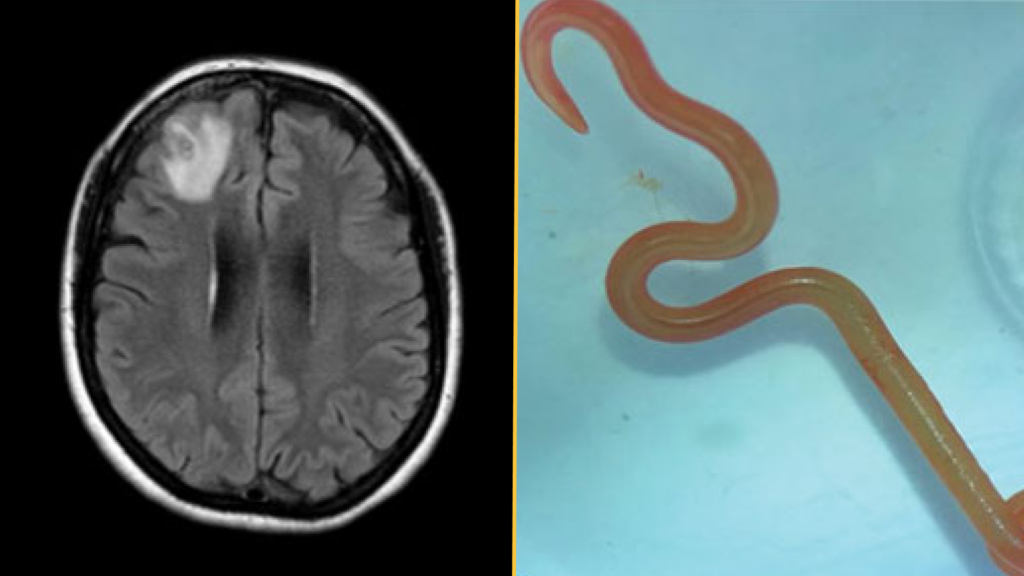

Diagnosis: Approximately one year after the first hospital visit, the woman began to show signs of depression and became forgetful. Doctors ordered an MRI scan of her brain, which detected a lesion in her right frontal lobe. An incisional biopsy was then performed to expose and examine the injured area. That’s when they discovered “string-like structures” inside the lesions, which they identified as live parasites called helminths, according to her case report.

The insect was bright red, approximately 3 inches (80 millimeters) long, and 0.04 inches (1 millimeter) thick.

Treatment: Doctors removed the worms from the woman’s frontal lobe and examined the surrounding tissue and found no parasites. They gave her two days of ivermectin, this time combined with four weeks of albendazole, a broad-spectrum drug used to treat helminth infections, to kill any remaining parasites in her organs.

What’s unique about this case: Doctors identified the worm as a third-stage larva of Ophidascaris robertzi, a parasitic nematode native to Australia. Although adults breed in the carpet python (Morelia spilota), the nematode can infect other animals during the larval stage of its life cycle.